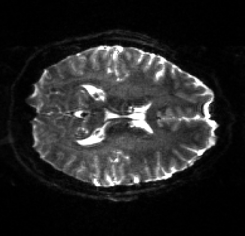

Table 6 reports the runtime and correction quality for PyHySCO using GN-PCG, HySCO, and TOPUP. On real 3T and 7T data, PyHySCO achieves lower loss and higher relative improvement between corrected images than HySCO, and higher relative improvement than TOPUP. The runtime on CPU for real data is 1-2 minutes for HySCO and over 1 hour for TOPUP, while PyHySCO on GPU has runtimes of 10-13 seconds. For the simulated dataset, PyHySCO requires an average of 1 minute on GPU, HySCO an average of 12.6 minutes on CPU, and TOPUP an average of 8.5 hours on CPU. Using the ground truth field maps from the simulated dataset, PyHySCO achieves the lowest average field map relative error, 14.48%, compared to 19.70% for HySCO and 16.36% for TOPUP. Figures 7, 8, and 9 show the field map and corrected images for one example subject from each dataset. The results of the methods are similar, and the resulting field maps are comparable to those of the existing tools, HySCO and TOPUP, while PyHySCO is considerably faster.

Refer to captionRefer to captionRefer to caption+vsubscript𝑣\mathcal{I}_{+v}inputRefer to captionRefer to captionRefer to captionPyHySCO (LBFGS)Refer to captionRefer to captionRefer to captionPyHySCO (GN)Refer to captionRefer to captionRefer to captionPyHySCO (ADMM)Refer to captionRefer to captionRefer to captionvsubscript𝑣\mathcal{I}_{-v}Refer to captionRefer to captionRefer to captionRefer to captionRefer to captionRefer to captionRefer to captionRefer to captionRefer to captionRefer to captionRefer to captionRefer to caption|+vv|subscript𝑣subscript𝑣|\mathcal{I}_{+v}-\mathcal{I}_{-v}|Refer to captionRefer to captionRefer to captionRefer to captionRefer to captionRefer to captionRefer to captionRefer to captionRefer to captionRefer to captionRefer to captionRefer to captionfield map 𝐛𝐛\mathbf{b}Refer to captionRefer to captionRefer to captionRefer to captionRefer to captionRefer to captionRefer to captionRefer to captionRefer to caption+vsubscript𝑣\mathcal{I}_{+v}TOPUPRefer to captionRefer to captionRefer to captionHySCORefer to captionRefer to captionRefer to captionvsubscript𝑣\mathcal{I}_{-v}Refer to captionRefer to captionRefer to captionRefer to captionRefer to captionRefer to caption|+vv|subscript𝑣subscript𝑣|\mathcal{I}_{+v}-\mathcal{I}_{-v}|Refer to captionRefer to captionRefer to captionRefer to captionRefer to captionRefer to captionfield map 𝐛𝐛\mathbf{b}Refer to captionRefer to captionRefer to caption